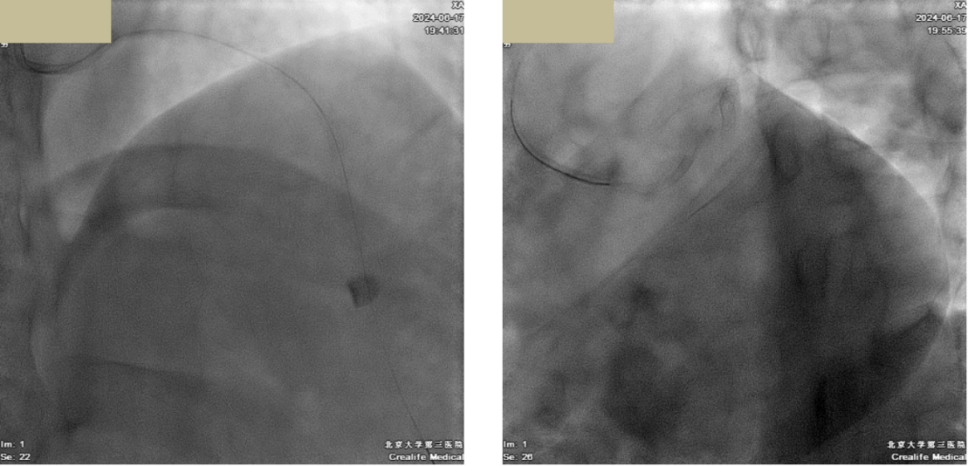

(1)冠脉造影:LM:正常;LCX:全程管腔不规则,近中段狭窄70%;LAD:开口狭窄50%,近中段长病变,最窄70%,D2近段狭窄30%~40%,可见LAD-RCA Ⅱ级侧支;RCA:近中段弥漫病变,狭窄70%~80%,PL闭塞;均衡型;于RCA近中段衔接置入2枚DES支架。

image.png

图2 RCA PCI术后

(1)冠脉造影:RCA原支架无再狭窄;LM正常;LCX全程管腔不规则,近中段狭窄60%~70%;LAD开口狭窄50%,近中段长病变,最窄70%~80%,D2近段狭窄30%~40%,可见LAD-PL2级侧支;于LAD近中段衔接置入DES支架2枚。

图3 LAD PCI术后